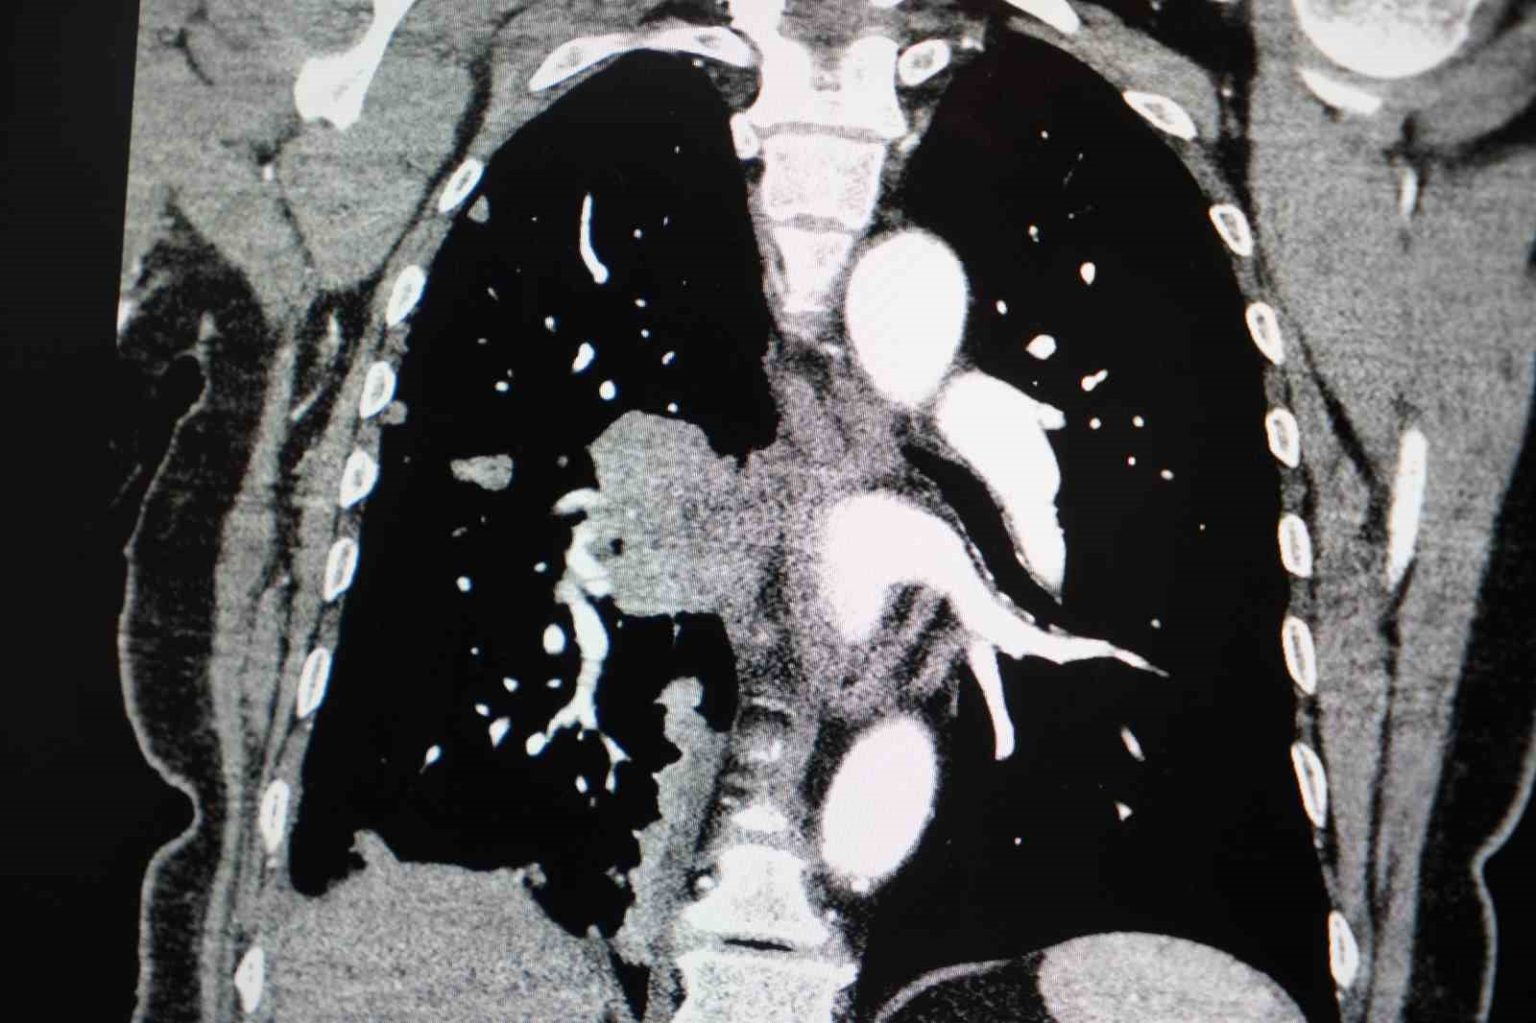

“Kadınlarda akciğer kanseri vakaları belirgin şekilde artıyor”

Akciğer kanseri vakalarındaki artışa da dikkat çeken Özkaya, “Son yıllarda hem sigara içen hem de hiç sigara kullanmamış bireylerde akciğer kanseri vakalarında dikkat çekici bir artış görüyoruz. Özellikle kadınlarda adenokarsinom tipi akciğer kanseri belirgin şekilde artış göstermektedir., Yapılan son araştırmalara göre akciğer kanseri teşhislerinin yaklaşık yüzde 20’si hiç sigara içmemiş bireylerde konuluyor. Bunun en önemli nedeni pasif içiciliktir. Yani siz sigara içmeseniz bile, yakın çevrenizde sigara içiliyorsa akciğer kanseri riskiyle karşı karşıya kalabilirsiniz” ifadelerini kullandı.